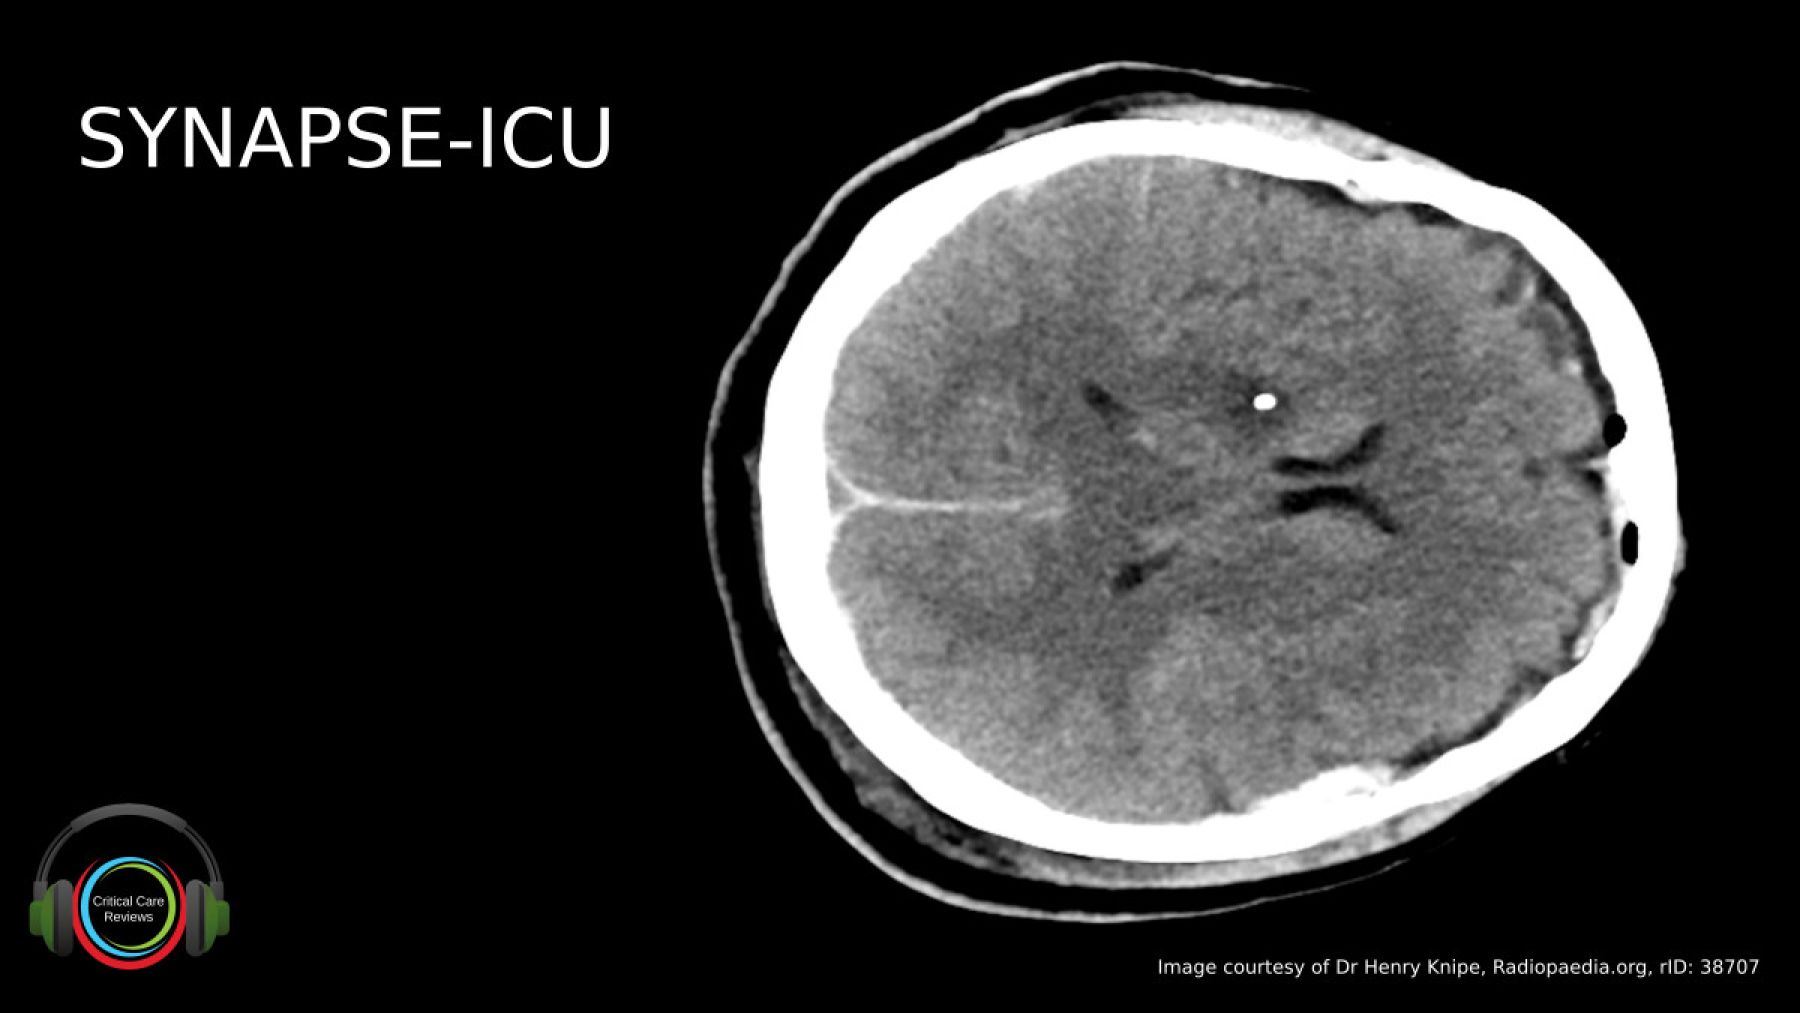

SYNAPSE-ICU Podcast

Recently, the global SYNAPSE-ICU observational study was published in Lancet Neurology. This work investigated the role intracranial pressure monitoring currently plays in the management of patients with acute brain injury. I spoke with the chief investigator, Prof Giuseppe Citerio from Milan.